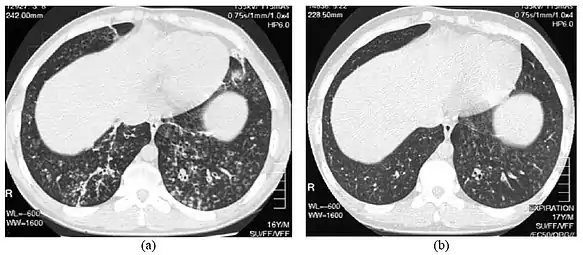

High-resolution computed tomography scan of the thorax

High resolution computed tomography (HRCT) images of the lower chest in a 16-year-old boy initially diagnosed with DPB (left), and 8 weeks later (right) after a 6-week course of treatment with erythromycin. The bilateral bronchiectasis and prominent centri-lobular nodules with a "tree-in-bud" pattern shows noticeable improvement.